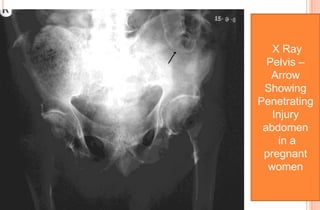

X Ray

Pelvis –

Arrow

Showing

Penetrating

Injury

abdomen

in a

pregnant

women

PENETRATING TRAUMA IN PREGNANCY

In one study, penetrating trauma accounted for 9% of all pregnant

trauma admissions

 Of those, 73% were handgun-, 23% knife-, and 4% shotgun related.

 Fall on sharp object and bull horn injury are common in rural Indian

 Penetrating trauma in pregnancy is associated with

- Increased foetal mortality (as high as 73%)

- Increased hospital stay,

- Complications such as intestinal perforation . Haemo peritoneum

due to intra abdominal organs like liver .spleen. Pregnant uterus. Big

vessels etc.